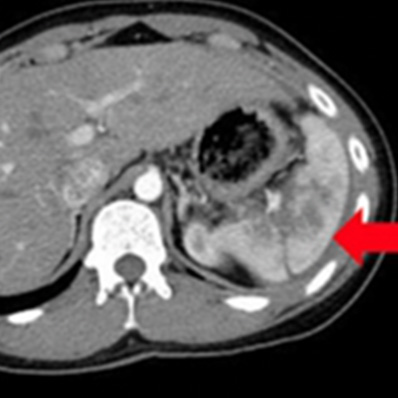

腹部大動脈瘤破裂

外傷性脾損傷

外傷による腹腔内出血